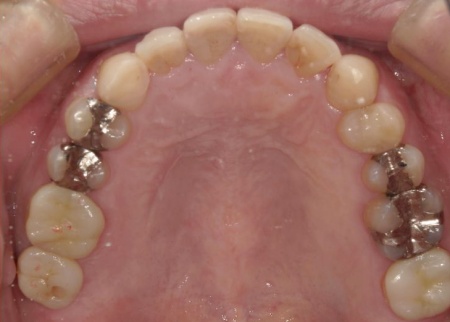

40代男性 虫歯治療やインプラント治療で口腔内全体を修復したあと部分矯正で噛み合わせを改善した症例

拝見したところ、複数の歯に虫歯が見られました。また、過去に治療した詰め物や被せ物が合わなくなっている部分や、歯が欠損している部位もあります。

右上の歯には、見た目が自然で耐久性の高いセラミック素材「e-max」を用いて、アンレー(歯の一部を覆う詰め物)による治療を行います。

詰め物が合っていない左上奥歯2本は、強度に優れたセラミック素材「ジルコニア」を用いた修復を計画しました。

・歯を削る量を最小限に抑える治療

前歯部は歯の温存を優先し、虫歯を除去したあとに白い詰め物「CR(コンポジットレジン)」で修復します。

右下奥歯3本と左下奥歯2本については、虫歯を除去したあとに歯科用樹脂を直接歯に盛り付けて形を整える「ダイレクトボンディング」を行います。

前歯部のCRやダイレクトボンディングは、周囲の歯の色調に合わせて材料を選択し、自然な見た目になるよう丁寧に仕上げています。